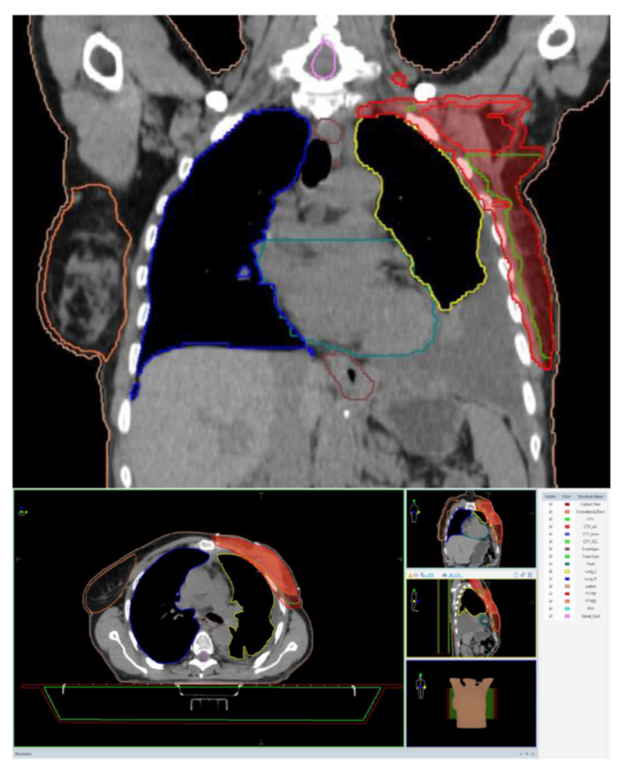

2. Case Report

| PTV50 | Median Planning Target Volume |

| Gy | Gray |

| Fx | Fractions |

| IMRT-VMAT | Intensity Modulated Radiotherapy—Volumetric Modulated Arc Therapy |